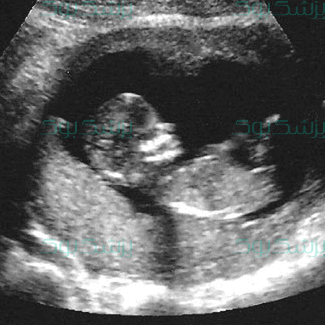

اصطلاح سقط جنین معمولا زمانی به کار میرود که از دست دادن بچه تا پیش از هفتهی 20 بارداری اتفاق بیفتد که آن را نارسایی اولیهی بارداری یا سقط خودبه خودی نیز مینامند. به طور تقریبی 15 الی 20% از بارداریها به سقط جنین ختم میشوند که بیشتر آنها در 12 هفتهی اول میباشند. پس در این دوران احتیاط و مراقبتهای لازم را به جا آورید زیرا تخمک بارور شده هنوز به درستی جنین را تشکیل ندادهاست.

همهی ما میدانیم که دوران بارداری، دوران بسیار حساسی به شمار می آید و باید شرایط مادر در طول این دوران به صورت مداوم توسط پزشک متخصص چک شود. پس مرتبا با پزشک مشاور خود در تماس باشید و اطلاعات خود را بروز نگه دارید. فراموش نکنید در شرایط شیوع ویروس کرونا (corona virus) زنان باردار جزو افرادی محسوب می شوند که در معرض ابتلای بیشتری قرار دارند.